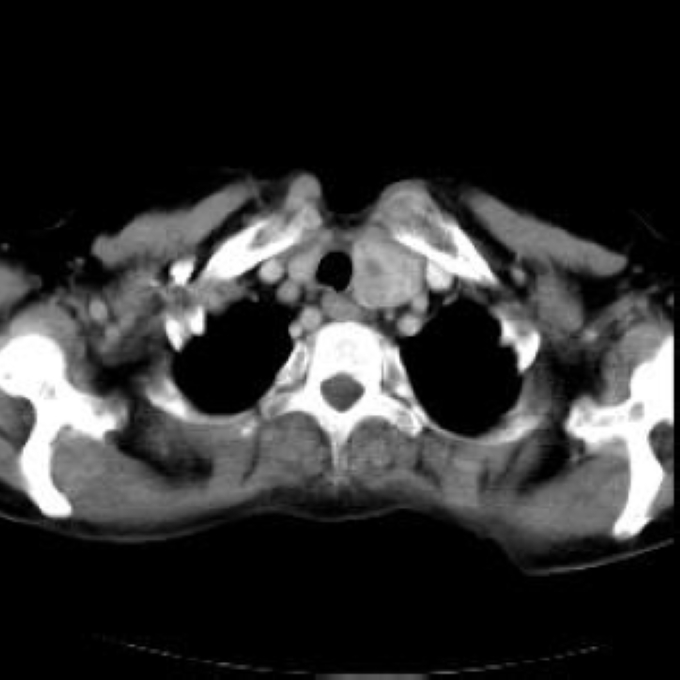

Arteria lusoria.

56 year old patient with dyspagia. A tumor of soft tissue was described in upper mediastinum on plain X-ray of the thorax. What is this mass in the upper mediastinum?